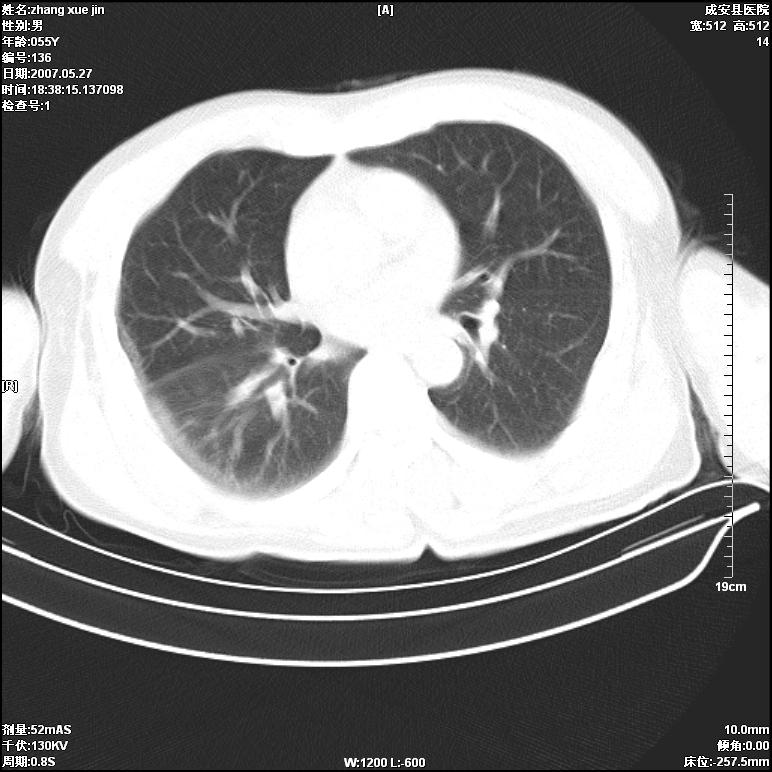

病人 男 53岁 从高处摔伤 行胸部ct检查,纵隔窗没事未上传,肺窗示,右侧胸膜下见条状稍高密度影,是胸膜下线还是右下肺轻度挫伤?意见不一,请分析。

右肺下叶胸膜下弧形窄带状模糊影,结合病史,考虑肺挫伤。

建议一周后复查,肺挫伤一般3~10天完全吸收。

左肺亦有,建议深吸气后扫描,你们是技术员扫描吧。

体位不正,左侧纵隔旁胸膜下亦见条带状略高密度影,考虑为坠积效应所致。